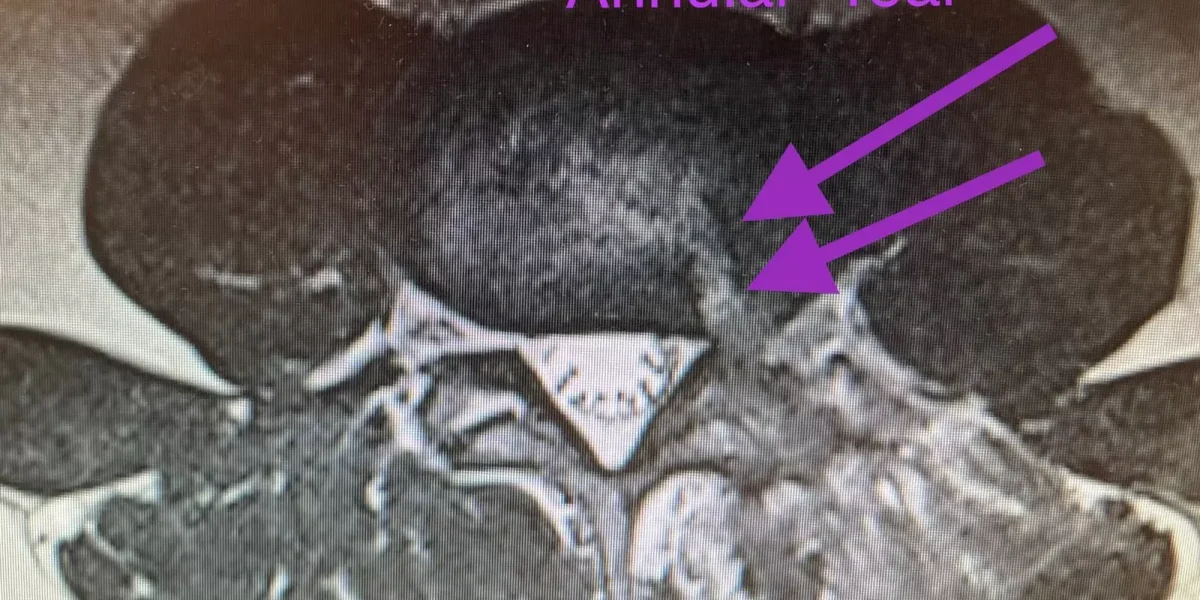

An annular tear develops when the annulus fibrosus, the firm outer tissue of a spinal disc, is damaged and splits open. The jelly-like inner core of the disc, known as the nucleus pulposus, squeezes out of the annular tear and into the spinal canal. It is quite common for an annular tear to be the first insult to a disc that results in a bulging disc. Bulging discs are herniated discs with small herniations of the nucleus pulposus. Through repetitive trauma to the disc, herniations get larger and frequently more symptomatic. Symptoms include back or neck pain, pain down the arm or leg, numbness, tingling and weakness.

An annular tear usually develops from trauma to the intervertebral disc. In its early stages, the tear may not cause any discomfort because the tissue still provides enough support to contain the nucleus pulposus in a painless state. However, as the crack opens wider, the disc’s gel-like central fluid may squeeze out (herniate) under increased pressure from normal activities like bending, jumping, lifting or twisting. This condition can cause high levels of pain and discomfort as we will discuss below.